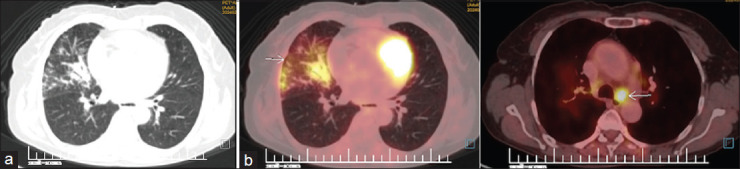

结节病是一种病因不明的复杂多系统疾病,表现为多种症状,常累及多个器官。声带麻痹是罕见的报告与结节病。由于纵隔淋巴结病压迫喉返神经而出现声带麻痹的病例报道很少。我们在此报告了3例因结节病引起的纵隔淋巴结肿大压迫喉返神经而导致声带麻痹的病例,并回顾了相关文献。

Sarcoidosis, is a complex multisystemic disease of unknown aetiology, which manifests via a variety of symptoms frequently affecting multiple organs. Vocal cord paralysis is rarely reported with Sarcoidosis. There have been very few case report of patients presenting with vocal cord palsy due to mediastinal lymphadenopathy causing compression of recurrent laryngeal nerve. We hereby report a case series of 3 patients presenting with vocal cord palsy due to recurrent laryngeal nerve compression by enlarged mediastinal lymph nodes due to Sarcoidosis and also reviewed the supporting literature.